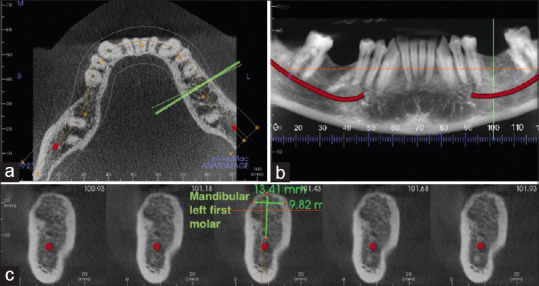

Materials and methods: CBCTs taken for implant placement were included. The heights and widths of edentulous ridges were measured with Anatomage in vivo dental three-dimensional software, and actual implant size data were retrieved from treatment notes. Central incisor, canine, first premolar and first molar locations were analysed. One-way analysis of variance (ANOVA) was run to determine the average sizes for edentulous ridges and implants and Pearson correlation was conducted to determine the accuracy of CBCT-based implant size prediction.

Results: Of 544 cases analysed, the average implant diameter was 4.17 mm (standard deviation [SD] =0.38) and the length was 10.05 mm (SD =1.17). Alveolar width and height were 3.74 mm and 4.31 mm larger than the implant diameters and lengths, respectively providing approximately 1.5-2 mm of extra space on either side of the implant in relation to adjacent anatomical structures. Implants placed at mandibular canine and first molar and maxillary first premolar demonstrated significant correlations with the sizes of the edentulous ridges (P < 0.05).